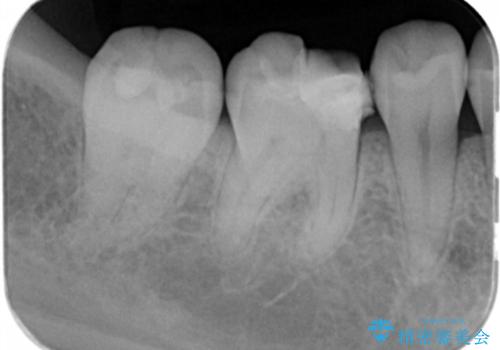

- 過去に退院で治療した詰め物が欠けたことにより来院。

古いプラスチックの樹脂、虫歯を全て取り除き

ジルコニアクラウンにて治療しました。